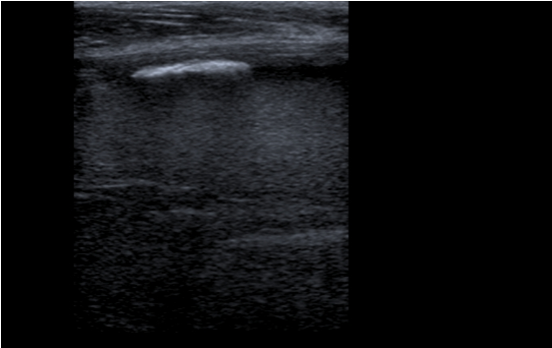

Hematoma no encapsulado de 5 x 9 cm en vasto intermedio, sin captación de doppler color y con aparición en bordes externos de calcificaciones con sombra acústica posterior.